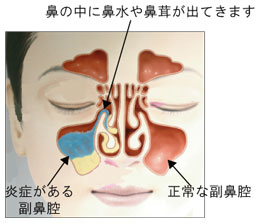

「院長、副鼻腔炎なんて大変だな~」と他人事に思っていたら、これまで鼻を患ったことなどないスタッフの私まで急性副鼻腔炎になってしまいました・・・。環境が似ているからでしょうか?蓄膿ともいうそうでショックです。

夜、寝ていると、鼻水が上から下へドロッと流れて気持ち悪いことこの上なし。重力を副鼻腔で感じられるとは知りませんでした。何かが流れるうちはまだいいのですが、出ずに溜まっていくと顔がむくんで、熱っぽくなって、頭痛がしてきて、そして全身の倦怠感に。そして寝ながらそんな変化を感じ取っているということは ⇒ ちゃんと寝てない ⇒ ストレスかかってる、そんなことなのでしょうか・・・。

副鼻腔炎になって生まれて初めて歯と顎が痛くなったのです!「これがよくあるアレか、これは痛い!」と初実感。鼻か歯か明白でない痛みを訴える患者さんや院長の辛さが少しだけ分かった気に。体の不調は辛いけど仕事にはプラスでした。そして現在、院長が手術したのと同じ耳鼻科医院でお薬をもらって様子を見ております・・・。

2016.7『院長慢性副鼻腔炎手術』

院長、幼少から鼻があまり良くないそうでこれまでに何度か手術経験があるとのこと。良くなるための手術とはいえ、一度メスを入れたところは弱くなるらしく手術した周辺が時間をかけて癒着してしまったとかそれで最近、鼻が通らず、体調も優れないので連休を利用して副鼻腔をひろげる手術を受けました。

入院ナシの手術でも術後は微熱や鼻血や涙目が続きさすがに診療するのが大変そうでした。院長がツライのはもちろん分かるのですが、実はスタッフも結構大変でした。なぜなら・・・院長、右の鼻にワッテを入れっぱなしなんです。診療中はマスクで見えませんが休憩時には顔が見えて仕方ない事だと分かってるんですが、どうしても笑いが込み上げてしまうのです!そういう意味で大変でした。院長スミマセン。

歯科と耳鼻科の領域はとても近くて、「歯の痛みかな?」と思ったら「実は原因は鼻だった」ということが多々あります。その点、院長自身、鼻を患った経験があれば歯と鼻の不調には大いに共感できるでしょう。なので手術は大変だったろうけど「仕事上、役立つな・・・」と他人事ながら思ったのでした。院長、本当にお疲れさまでした。